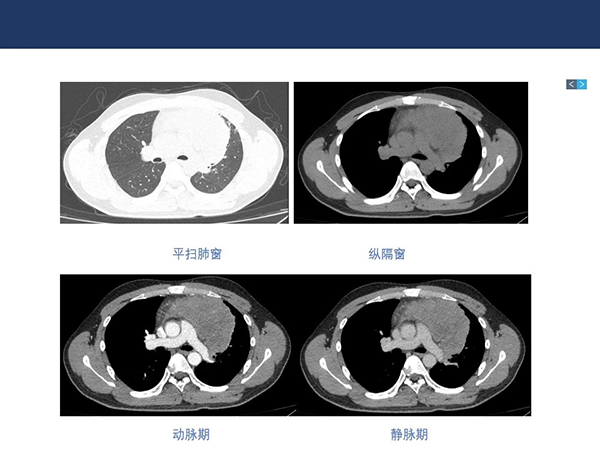

【院庆51周年】放射科:纵隔淋巴瘤